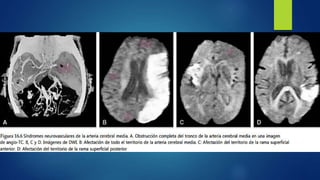

Síndromes neurovasculares de

arteria cerebral media

 Oclusión del TRONCO COMÚN:

 Oclusión de la RAMA

SUPERIOR:

 Hemiplejía y hemianestesia contralateral.

 Hemianopsia homónima contralateral.

 Desviación conjugada de la cabeza y ojos hacia lado de lesión.

 Anosognosia e inatención somatosensorial contralateral.

 Si obstracción ocurre en hemisferio dominante se añade afasia

global.

 Pérdida de consciencia (ocurre raramente como sx inicial, pero

aparece en días siguientes si se desarrolla un edema cerebral).

 Déficit sensitivomotor contralateral de predominio

faciobraquial (por afectación de la corteza)

 Oclusión del RAMA

INFERIOR :

 Oclusión de las RAMAS

PROFUNDAS :

 Hemi o cuadrantanopsia homónima superior contralateral

 Afasia de Wernicke si se afecta el hemisferio dominante, se

puede originar una sordera pura para las palabras.

 Si isquemia en lóbulo temporal es extensa puede aparecer un

estado confusional con agitación >fcte. en lesiones derechas.

 Hemiplejía contralateral

 En lesiones extensas una hemianopsia homónima

contralateral

 Hemicorea y hemibalismo agudos por afectación de núcleos

de base